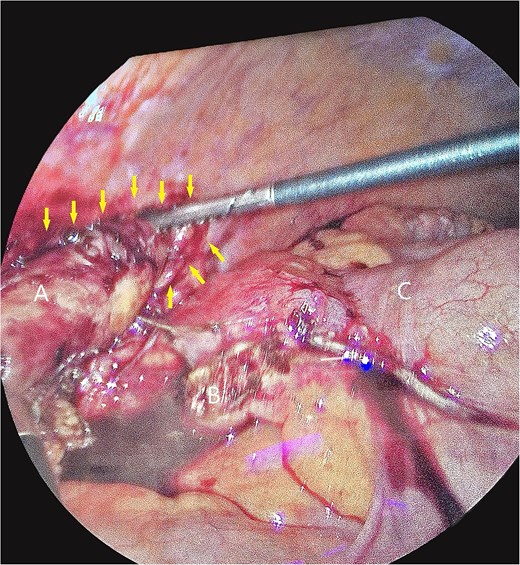

The patient underwent laparoscopic appendectomy with laparoscopic enterolysis. The appendix appeared inflamed, dilated, and gangrenous, with a perforation located 2 cm from the base. Notably, the appendix was not in a retrocecal position as initially suspected but was found to be herniating through a defect in the iliacus muscle (Fig. 3). The appendix was circumferentially freed from the hernia defect, which was identified as tracking cephalad between the iliacus muscle and the iliac bone. The hernia defect measured 2.5 cm and was primarily closed using two figure-of-eight 2–0 Vicryl sutures, leaving a small inferior opening to allow for drainage (Fig. 4). A 19 Fr Blake drain was placed in the right lower quadrant and paracolic gutter.

Intra-operative photos of appendix contained within iliacus hernia after appendix was divided. The arrows showcase the hernia with appendix. (A) Appendix, (B) mesoappendix after division, (C) cecum with staple line.